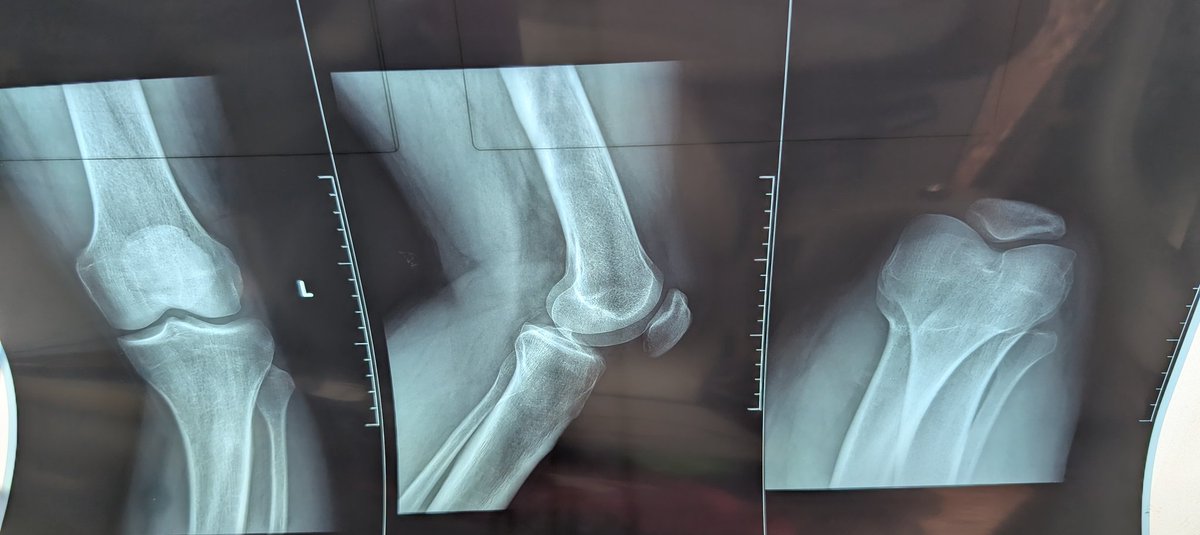

We all dread this day, especially if you run on gravel, because as surely as day turns to night, an injury will come. Yesterday morning, I suffered a hard and painful fall less than 2 kilometers into my run, injuring my left knee and the fingers on my left hand. I tried to run again and shake off the pain, but I couldn't go beyond another 2 kilometers because of the pain and discomfort. Sensing defeat, I walked back home, bruised from the fall but more battered by my thoughts about how I'll participate in the @MakRun_Ug, @RwenzoriMarathn, and #RotaryCancerRun. As I recuperate and hope nothing's too serious, I'll remember my words: movement is a privilege, so don't take it for granted. Walk, run, swim, or jump while you still can.